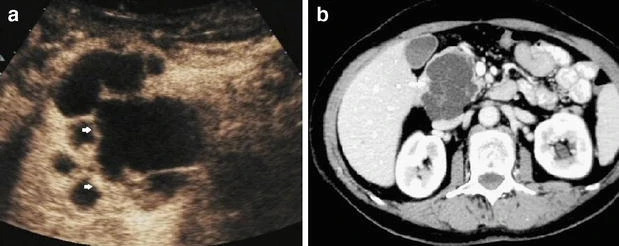

In the sequel, to describe our approach, we will mainly focus on the acoustic imaging using micro-bubbles, i.e. (1), and the photo-acoustic imaging using (dielectric) nano-particles, i.e. (3). In Figure 1 and Figure 2, we see the sharpness of the images when injecting nano-particles or micro-bubbles respectively in the targeted regions. This suggests, in particular, that contrasting the images taken before and after injecting the small-scaled contrasts agents would allow us to extract quantitative information on the targeted regions, as the mass density and the bulk modulus, for the acoustic imaging, or the electric permittivity, and eventually the conductivity, for the photo-acoustic imaging of the targeted region. Our aim is to understand and quantify this.

Refer to caption

Figure 2. (a) Multilocular pancreatic cystic mass revealing intracystic septal enhancement 454545 s after micro-bubble injection with ultrasound. (b) The pattern is confirmed at contrast-enhanced CT. This figure is from [56].